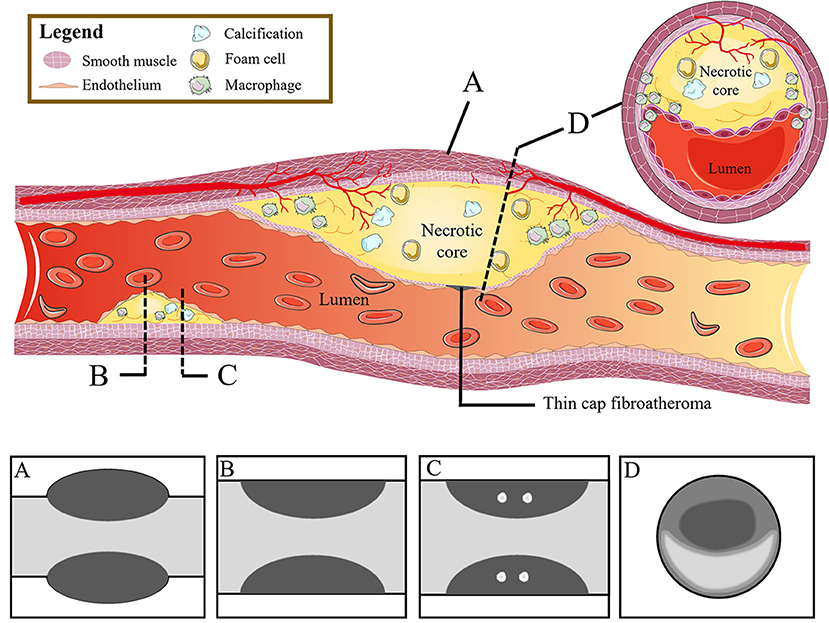

The characteristics of high-risk plaques are related to the vulnerability of plaques (18). Based on the histopathologic composition of vulnerable plaques, including thin cap fibroatheroma, macrophage infiltration, and necrotic core (20, 21), the corresponding typical manifestations of high-risk plaques in CCTA are listed as follows: positive remodeling, low attenuation, spotty calcification, and napkin-ring sign (22–24) (Figure 1).

Figure 1. From high-risk plaque histopathology to CCTA. The figure shows the histopathologic components of vulnerable plaques (colored illustrations) and the corresponding typical CT features of high-risk plaques: (A) positive remodeling, (B) low attenuation, (C) spotty calcification, and (D) napkin-ring sign. CCTA, coronary computed tomography angiography.

Clinically, coronary artery remodeling refers to be the compensatory changes of cross-sectional area and structure of coronary artery in the progression of coronary atherosclerosis. In pathological findings, the lumen of some coronary arteries was found to be increased during atherogenesis in autopsy (36). For in vivo detection of coronary artery, IVUS examination confirmed that the cross-sectional area of the vessel at the atherosclerotic site was significantly larger than that at the proximal reference segment, then the concept of positive remodeling was proposed which refers to the compensatory increase of vessel wall when atherosclerotic plaque volume increases continuously, thus maintaining the effective area in the lumen (37). While on CT, the outer vessel wall dimension could be measured. The remodeling index (RI) is calculated by dividing the vessel cross-sectional area/diameter of the largest stenosis (or maximum vessel area/diameter) by the average cross-sectional area/diameter of the proximal and distal reference segments (7, 38, 39) (Figure 2Aa). At present, positive remodeling is generally defined as RI ≥ 1.1 in CCTA (8, 40, 41), while some researchers prefer other cut-off point (42, 43). In addition, automatic software makes it easier to quantify the RI (44).

Low Attenuation

The composition of plaques can be reflected by CT attenuation value, with the highest CT attenuation value for calcification, followed by fibrous tissue, and the lowest CT value for lipid. Low-attenuation plaques refer to those with the lowest CT attenuation value and the most easily ruptured lipid composition (a lipid-rich necrotic core), which is defined as mean attenuation <30 Hounsfield units (HU) of at least three regions of interest (ROIs) in general (39, 45) (Figure 2Bb). However, the CT attenuation value of lipid plaques overlaps with that of fibrous plaques, so it is difficult to distinguish the plaques only by CT attenuation value alone. In addition, the CT value of plaques is affected by many factors, such as contrast agent, plaque volume, slice thickness, tube voltage, and so on. Therefore, the current research mainly relies on special procedures to identify which plaque is low-attenuation (7, 45).

Spotty Calcification

Spotty calcification is the initial state of calcification. Since calcification is one of the consequences of local inflammation, spotty calcification may indicate active local inflammation. Mechanical stimulation on fibrous cap caused by spotty calcification and local inflammation may lead to the plaque with spotty calcification easy to rupture, thereby accelerating disease progression (46–48). Therefore, spotty calcification is considered to be one of the characteristics of high-risk plaques. In CCTA, spotty calcification is generally manifested as calcification in plaques with a density of more than 130 HU and a diameter of <3 mm surrounded by non-calcified components (42, 49, 50) (Figure 2Cc). However, only calcification more than 0.5 mm in diameter is visible on CT, so nearly two-thirds of the calcifications cannot be recognized on CT (51, 52).

Napkin-Ring Sign

The napkin ring sign is a qualitative plaque feature that can be defined by the presence of two features on the cross section of non-calcified plaques: the low-attenuation central area obviously contacting with the coronary artery lumen and the annular high attenuation plaque tissue surrounding the central area (7, 34) (Figure 2Dd). Histologically, the low-density area corresponds to the large necrotic nucleus, while the “annular” outer area is associated with fibrous tissue. The necrotic core area in plaque with the napkin-ring sign may be more than twice that without napkin ring sign (1.10 vs. 0.46 mm2) (53) corresponding to some studies' indications that a necrotic core area >1 mm2 when plaque is prone to rupture (14). The density of the ring is greater than that of the inner core but <130 HU in CT scans. Currently, the napkin-ring sign is considered to be a special CT feature of plaque with a large necrotic core, and it is a reliable marker of plaque instability (7, 14).